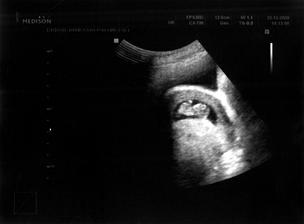

22.12.2009 (10.tt) - Ultrazvuk: viděli jsme naše miminko, slyšeli poprvé bušit srdíčko a máme první fotečku.